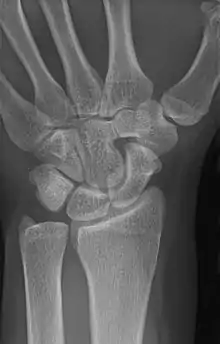

Carpal coalition

An example of a lunotriquetral coalition, the most commonly fused carpal bones

Carpal coalition is the abnormal fusion of two or more carpal bones when they fail to segment during intrauterine development.[1] First described by Eduard Sandifort in 1779, carpal coalitions are often an isolated issue which connect two carpal bones in the same row of the wrist.[2] These issues are congenital and occur at various rates throughout the population.[3]

The lunate and triquetral bones are the most common carpal bones to fuse together, resulting in a lunotriquetral coalition in 1% of people. 60% of patients with a lunotriquetral coalition will have it bilaterally.[1] Among isolated incidents the capitate and hamate bones are the next most common to fuse followed by the pisiform-triquetrum, trapezium-trapezoid, scaphoid-capitate, and triquetrum-hamate.[3]